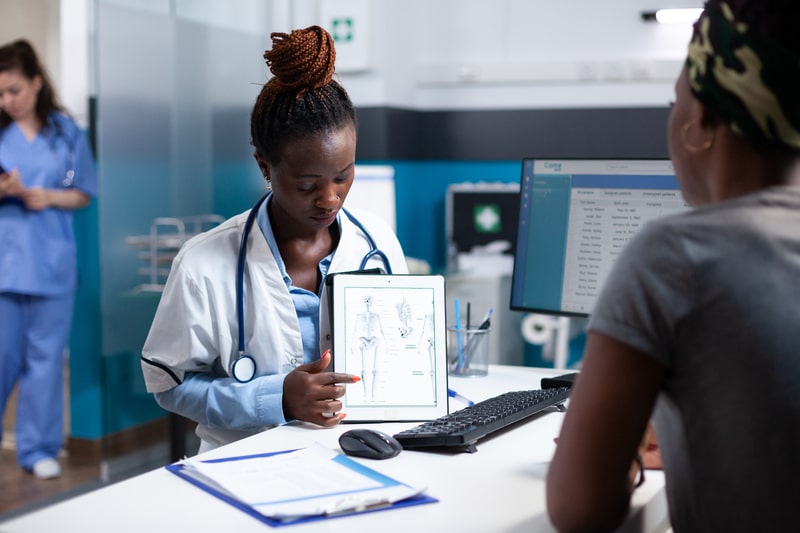

Como é feito o diagnóstico da doença óssea de Paget?

A maioria dos portadores da doença óssea de Paget não apresenta sintomas evidentes.

Sendo assim, muitas vezes, o diagnóstico é incidental, realizado através de radiografias ou exames de sangue realizados por outros motivos, que revelam sinais da condição.

Em alguns casos, pode ser necessário encaminhamento a um endocrinologista ou reumatologista.

Durante o exame físico, o médico avaliará as áreas do corpo que causam desconforto, podendo solicitar radiografias e exames de sangue para confirmar o diagnóstico da doença óssea de Paget.

Para identificar alterações nos ossos, são realizados testes de imagem.

As imagens revelam áreas de fraturas, aumento ósseo e deformidades características, como curvaturas nos ossos longos.

A varredura óssea é bastante solicitada nesse sentido. Consiste na injeção de material radioativo no corpo do paciente, permitindo a visualização das áreas mais afetadas nos ossos, que se destacam nas imagens da varredura.

Os testes laboratoriais também são úteis no diagnóstico, uma vez que pessoas com a doença apresentam níveis elevados de fosfatase alcalina no sangue, o que pode ser detectado por meio de exames de sangue.

Esses resultados podem contribuir para confirmar a presença da doença óssea de Paget.